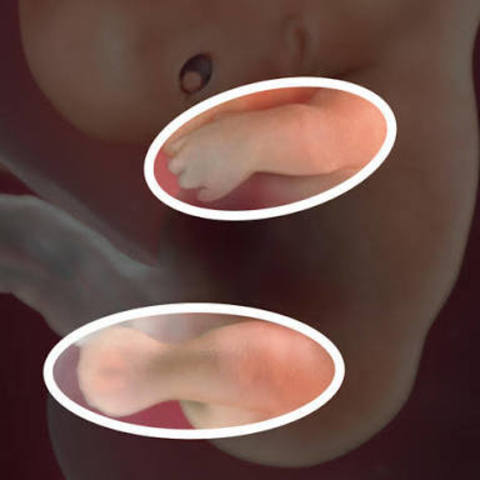

Las piernas y los brazos aún no sobresalen mucho pese a todo el proceso anteriormente mencionado. No obstante a esto, sus dedos de las 4 extremidades comienzan a asomarse.

El cuello, la cara y los dedos comienzan a moldearse.

Aparecen las orejas y también los párpados.

Sólo hay un orificio para la boca y la nariz. Se forman brotes dentales y el nervio óptico comienza a funcionar.

El embrión ya tiene párpados, labio superior y la nariz y las orejas se están empezando a formar.

El cuerpo se está alargando, pueden reconocerse lo que serán brazos y piernas, y es posible ver el esqueleto a través de su piel, que es translúcida.

Alrededor de sus órganos internos van a empezar a formarse las costillas. Aparecen las rodillas y los codos. Los brazos, piernas y dedos se ven mejor.